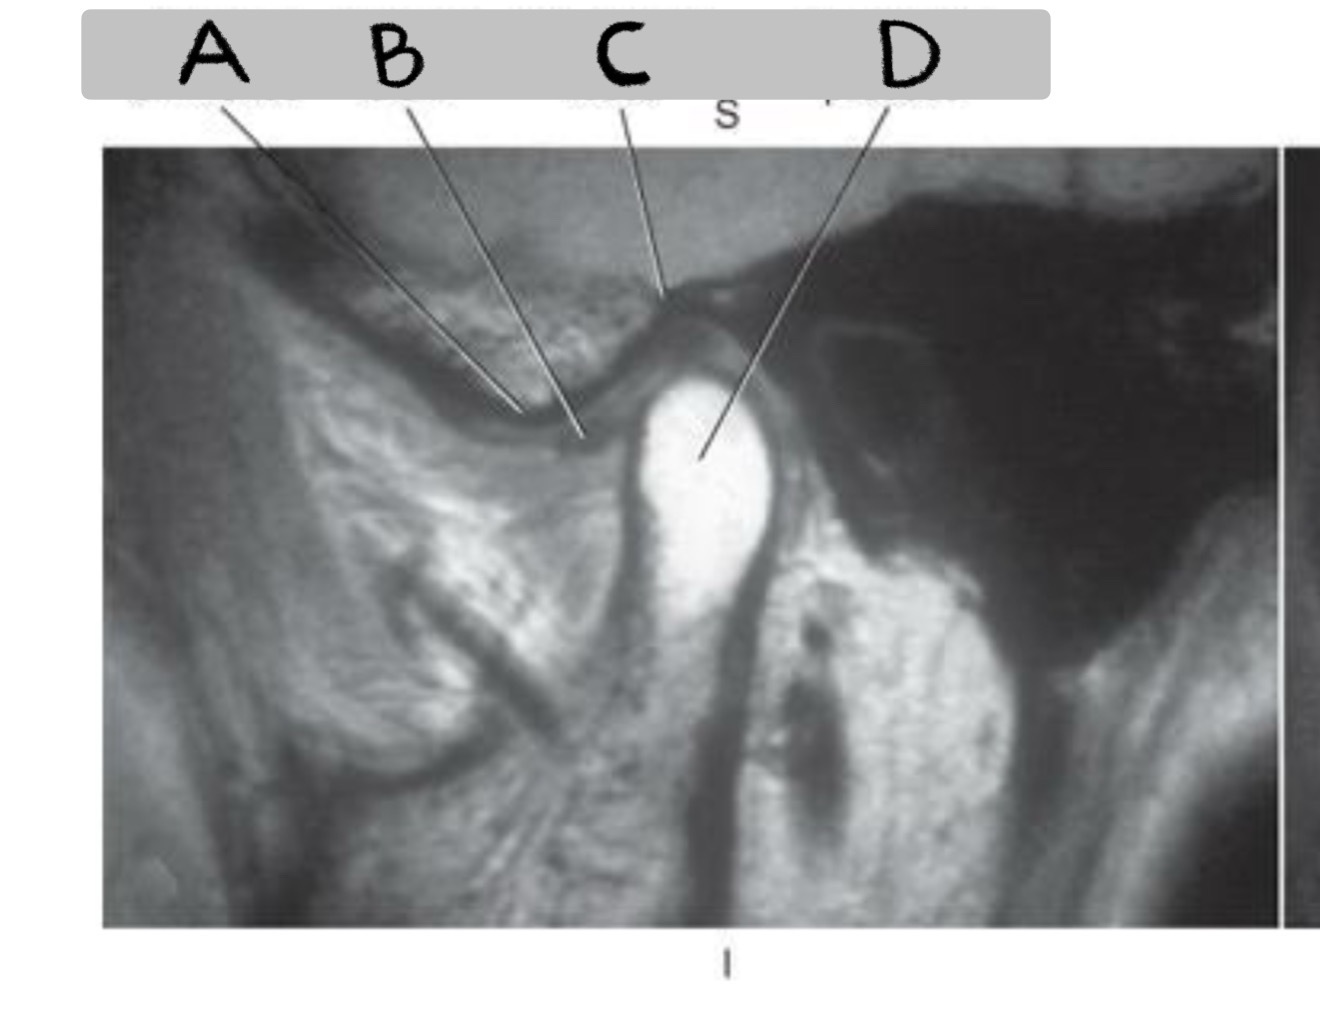

12

MATCH

Mandibular fossa

Condyloid process

Articular eminence

Articular disk

A

C - Mandibular fossa

D - Condyloid process

A - Articular eminence

B - Articular disk

13

What plane

Sagittal oblique TMJ (closed vs. open mouth)

What imaging plane(s) used for TMJ closed mouth?

Axial, Coronal oblique, Sagittal oblique

MATCH 1. Mandibular condyle 2. Articular tubercle 3. Articular disk

A Mandibular condyle B Articular disk C Articular tubercle

Match: 1: Mandibular condyle 2: Articular tubercle 3: Articular disk

A. Mandibular condyle B. Articular disk C. Articular tubercle